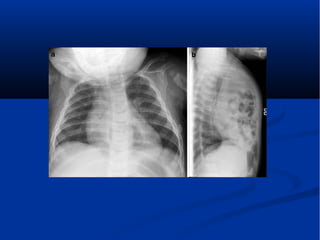

 A 2-week-old boy with Morgagni defect

presenting with respiratory difficulty.

Anteroposterior (a) and lateral (b) chest

radiographs show intrathoracic bowel herniating

through an anterior foramen of Morgagnidefect

A 7-day-old boy with a